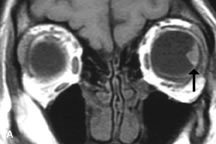

Extraocular muscle enlargement in patients with thyroid-associated orbitopathy is demonstrated equally well with CT and MRI studies. However, the superior tissue contrast on MR images reveals better details of the relationships of the optic nerve to the thickened muscles at the orbital apex (Fig. 16).50 In addition, MRI may be able to differentiate between muscles that are enlarged as a result of edema and active inflammation and those enlarged because of fibrosis by their T2 relaxation times.21 Quantitative MRI was not found to be accurate in predicting the success of low-dose orbital irradiation.51 However, a muscular index relating the diameters of the rectus muscles to the bony orbital dimensions was useful in predicting optic nerve compression.52

Fig. 16. A-C, T1-weighted MR scans obtained with a high-resolution surface coil demonstrate fusiform enlargement of the extraocular muscles. The medial, lateral, and inferior rectus muscles are especially involved. Note the relative sparing of the tendinous insertions, a finding characteristic of this disease process, as well as fatty infiltration of the lateral and inferior rectus muscles. There is marked proptosis, best visualized on the sagittal image (A), and mild crowding of the optic nerve at the orbital apex.